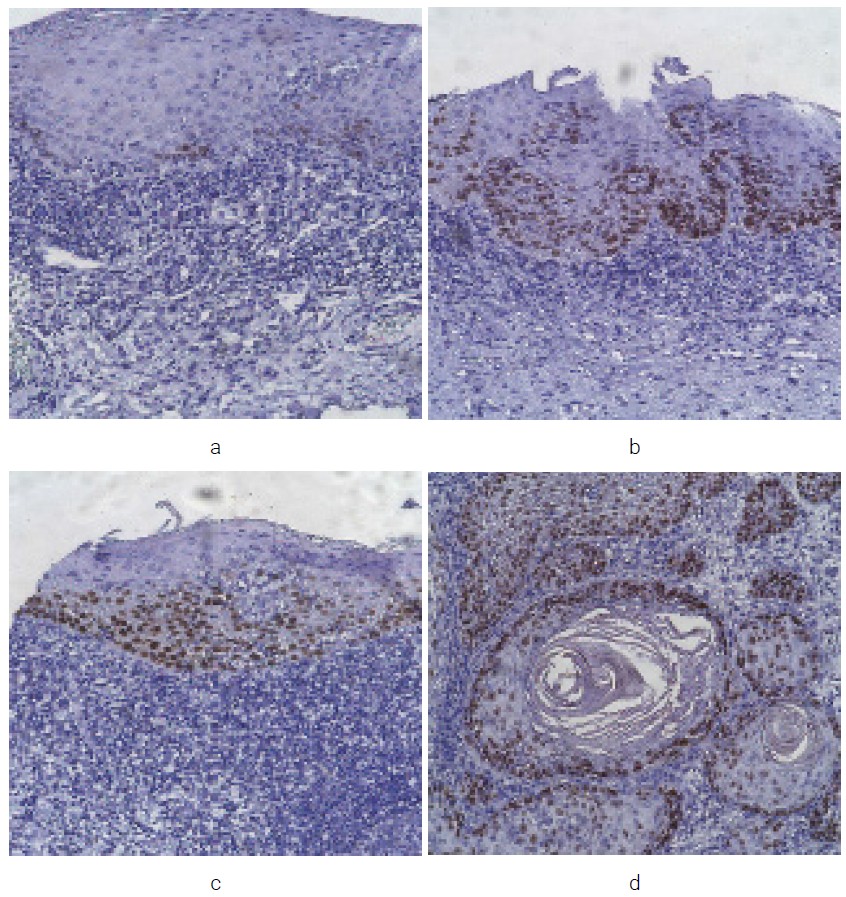

In routine examination with hematoxylin and eosin in the first group (EH), an increase in the number of epithelial cells was noted against the background of chronic inflammation in the lamina propria of the oral mucosa. Parakeratosis and hyperkeratosis were observed in the upper layers, while no atypical cells were detected. In the second group (LGED), a few polymorphic cells were found in 1/3 of the epithelial layer, with disrupted cell stratification but preserved cell differentiation in the upper layers of the epithelium. In the third group (HGED), cell nuclear polymorphism and increased mitosis of cells in 2/3 of the epithelial layer were noted. In the fourth group (SCC), changes in epithelial cells were observed, namely: complete loss of stratification and structure, and differentiation. Increased mitosis and pronounced nuclear-cytoplasmic ratio were observed. Altered cells formed complexes, with a higher number of atypical cells found in the non-keratinizing type of SCC In the keratinizing type of SCC, the presence of “keratin pearls” was noted. Pronounced infiltrative growth was observed in both cases of PR (Figure 1: a, b, c, d).

Fig. 1. Morphological characteristics of the oral mucosa in hyperplasia (a), low-grade dysplasia (b), high-grade dysplasia (c) and squamous cell carcinoma (d). Staining with hematoxylin-eosin (x 100)